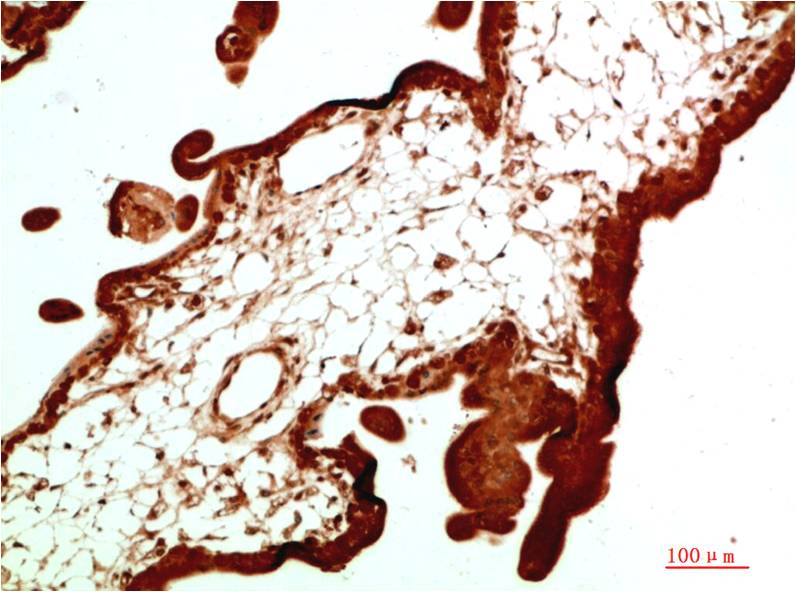

Acetyl P53(K382) Mouse Monoclonal Antibody(5H10)

Applications :IHC

| Recommended dilutions: | IHC: 1:100-200 |

| Specificity: | The Acetyl P53(K382) Mouse Monoclonal Antibody can detects endogenous Acetyl P53(K382) proteins. |